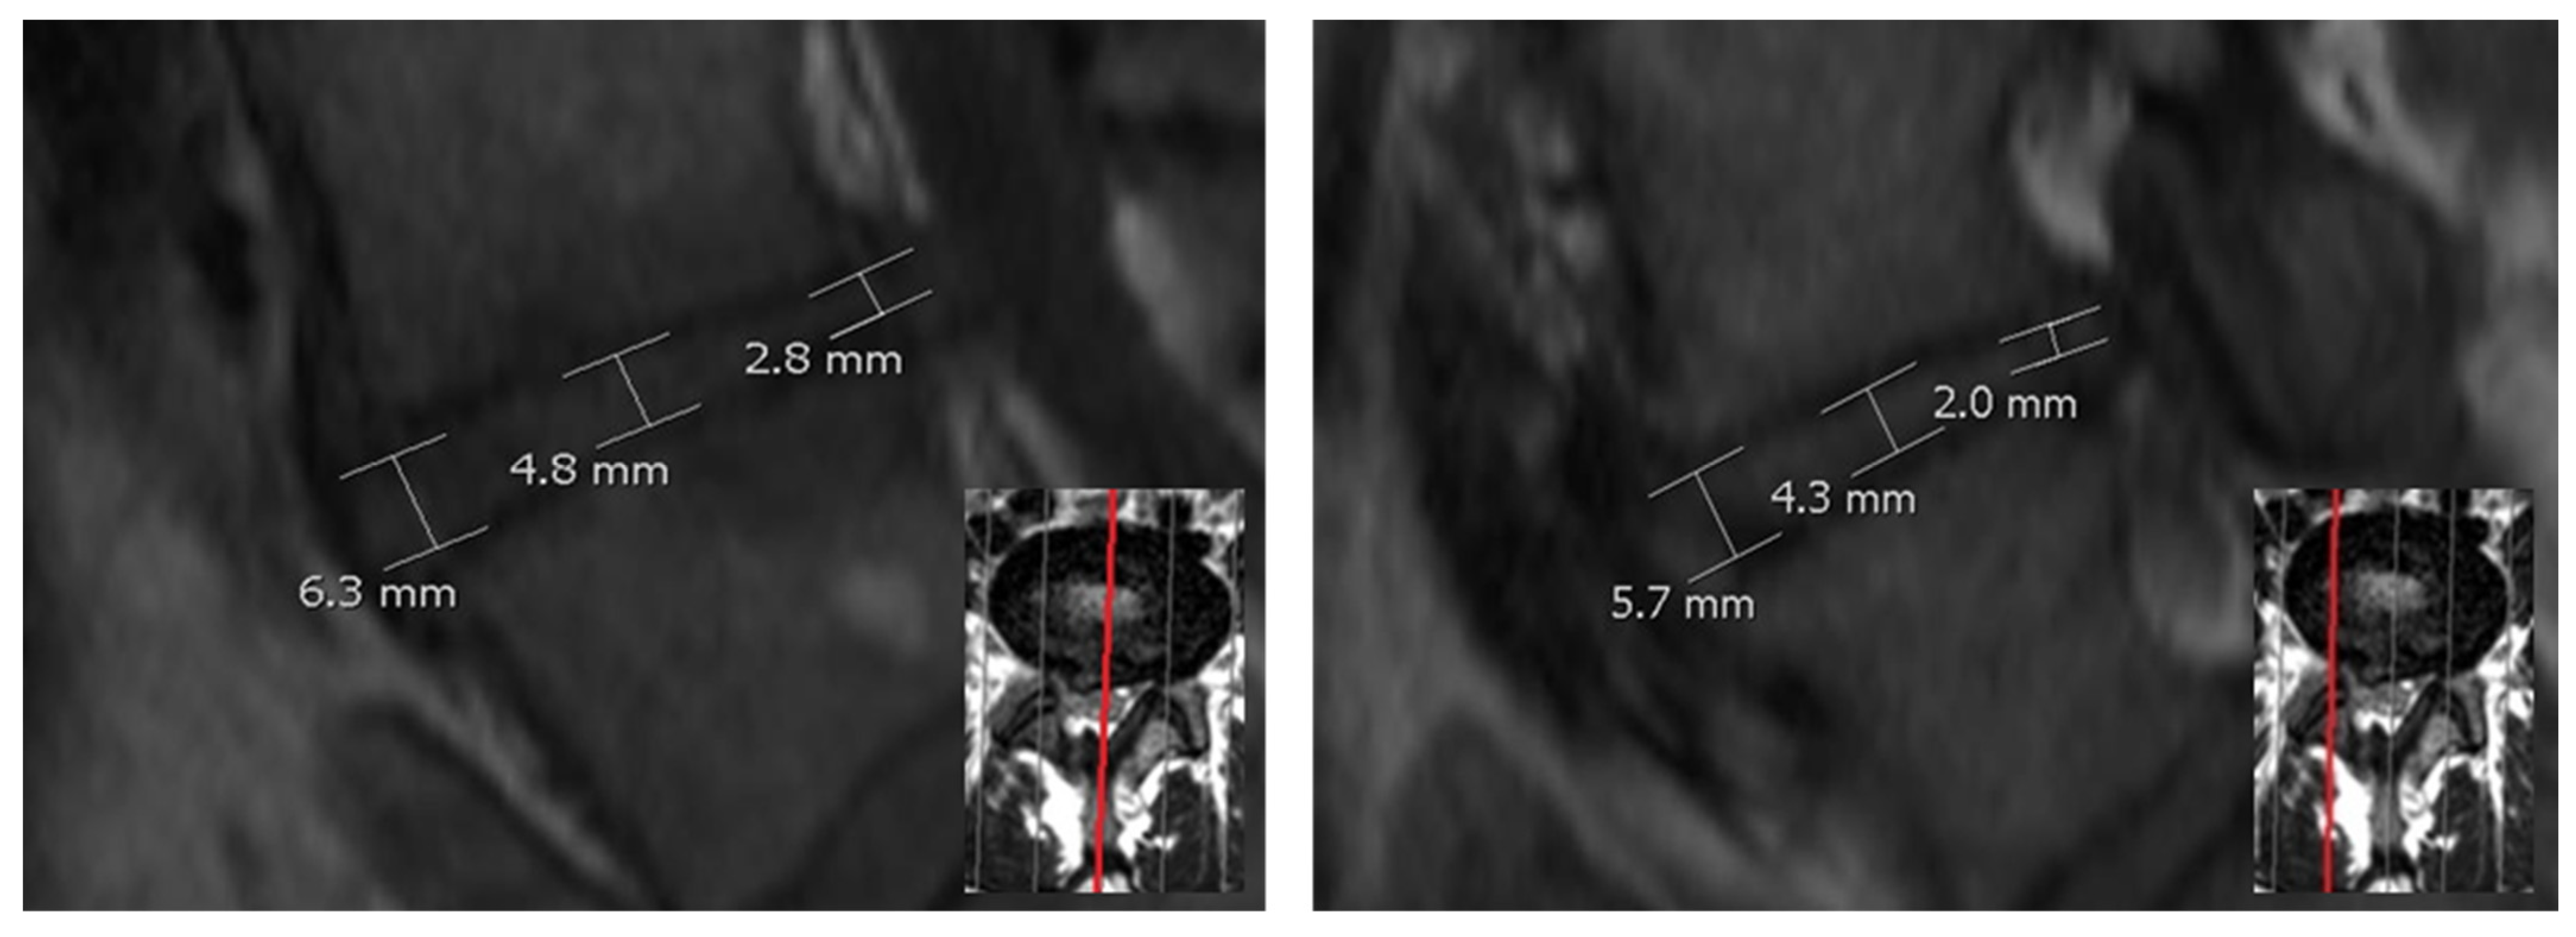

Three different heights of the lumbar discs, respective height measurement methods, denoted as H1, H2 and H3 have been used. Height H1 of the discs was measured in the center (visual center between the anterior and posterior intervertebral disc space) in the midsagittal plane (Figure 1).

Height H2 was calculated as the mean of the anterior (ventral) and posterior (dorsal) measured disc height in the midsagittal plane. Height H3 was obtained by calculating the mean of nine measuring points (including the measuring points of H1 and H2). The nine measuring points were measured at the midsagittal and two parasagittal sequences running through the pedicels of the vertebrae (see Figure 2). To ensure a better reliability of the method, the following aspects were to be followed during a measurement of H1–H9. Figure 1 follows these rules: The endplates were not included. The caudal vertebrae formed the basis of the disc height at the posterior and anterior margin. Potential osteophytes were excluded. When in doubt of which part of the vertebral body was an exophyte and which was the bony endplate, an imaginary line was drawn parallel to the vertebral body contour. Bulges or protrusions of the disc should not be included in the measurement. To be certain of measuring the intervertebral disc space between the vertebral bone, the visual presentation of the vertebrae and disc can be taken into account in axial planes. In each sequence, anterior, central and posterior heights were recorded. The lines drawn to examine heights H1, H2 and H3 were perpendicular to the adjacent cover plate.

Figure 1. Left image: Measurement of disc height for the methods H1 (disc height in the center) and H2 (mean of anterior and posterior disc height) midsagittal (red line). Right image: Example of the H3 method using additional parasagittal (red line) layers.